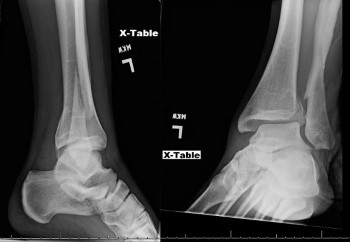

X-Ray Results

Left Ankle Xray: Left trimalleolar fracture with oblique fractures of posterior tibia and distal fibula with posterior-lateral displacement of fragments.